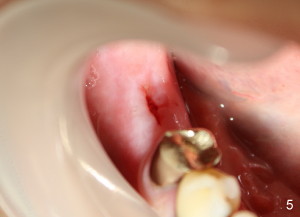

Mr. Lip returns to clinic for #30 and 31 implant placement. At the time of impression, there is no sign of gingival swelling around the tooth #19 (Fig.1: >; although the tooth has suspected root fracture). The patient requests keeping this affected tooth as long as possible while #30,31 implants are being placed and restored. This is not the case at the appointment of implant placement on the other side (Fig.1': *). There is localized gingival erythema and edema at the ML line angle. It appears that the treatment plan should be changed: the number of implants to be placed should be reduced from two to one and the infected tooth should be extracted to decrease the chance of implant infection. These two procedures are intended to be done at the same time so that bone harvested from #30 implant osteotomy (Fig.2) can be saved (Fig.2': < in dapen dish) and grafted in #19 sockets (Fig.3', 4'), particularly in the mesial one with severe bone loss due to root fracture.

Postoperatively, there is minimal pain for Mr. Lip. The patient rinses with Chlorhexidine, although he does not take Amoxicillin. Luckily, there is no sign of infection either in #30 implant placement area (Fig.5, wound dehisces after suture removal), or in the extraction sockets (Fig.5'), one week postoperatively.